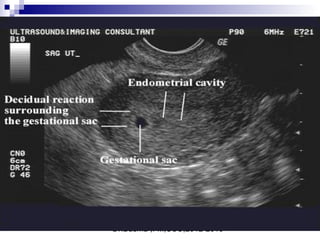

Double-decidual sign (5 weeks menstrual age). The decidua vera (dv) can be discerned

from the decidua capsularis (dc) and chorion laeve surrounding the gestational sac. A

small subchorionic hemorrhage(*) is present between the unapposed layers of

deciduvera.

 The "Double Decidual

Sign"consists of two

echogenic rings

surrounding the

hypoechoic gestational

sac.

 The inner ring represents

the chorion, embryonic

disc and decidua

capsularis (*). The outer

ring represents the

decidua parietalis (**).

Dr.Basma ,FM,SCU,2012-2013

Double ring appearance